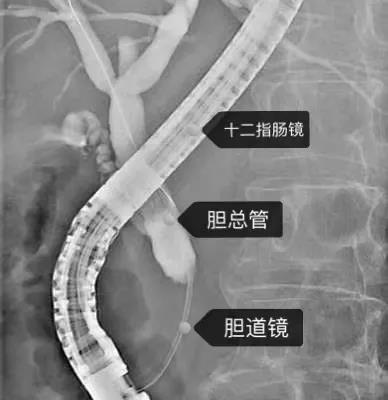

X線下操作示意圖

膽道鏡位于左右肝管分叉處

經(jīng)口膽道鏡診療技術(shù)是通過十二指腸鏡將膽道鏡送入膽胰管直視管腔內(nèi)部,從而完成對膽胰疾病診療的技術(shù)。該技術(shù)可使人體膽胰管結(jié)構(gòu)進(jìn)行動態(tài)清晰的可視化觀察,并可進(jìn)行活檢及治療,具有高清晰圖像、纖細(xì)管徑、大直徑活檢通道、精細(xì)化診療器械、操作靈活等特點。